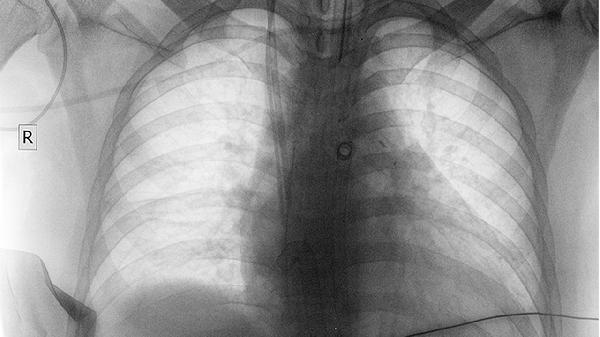

影像学检查是诊断气管和肺部疾病的重要手段,包括胸部X光、CT扫描等。这些检查可以清晰显示气管和肺部的结构,帮助医生发现炎症、肿瘤、积液等异常。根据检查结果,医生会制定相应的治疗方案。